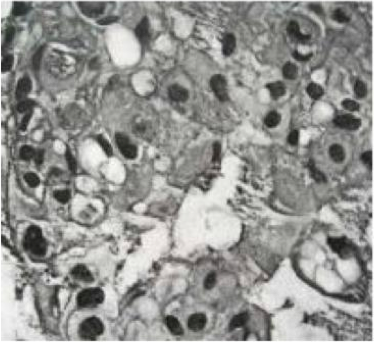

Berikut ini adalah gambar yang menunjukkan

A. Ependymoma

B. GBM

C. Medulloblastoma

D. Meningioma

E. Schwannoma

B